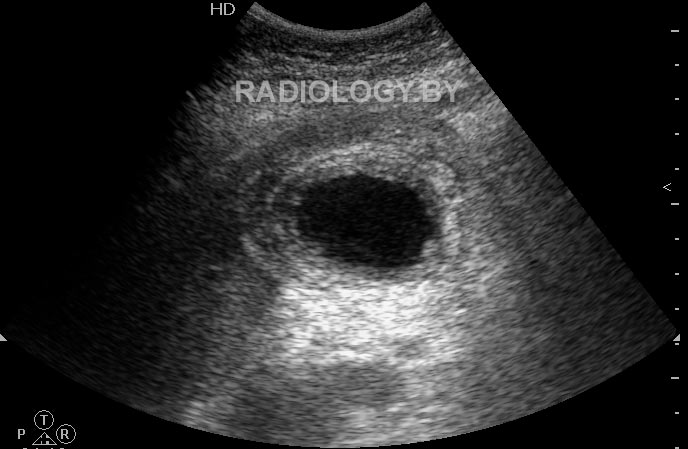

Re: Диффузное утолщение стенок желчного пузыря

Таким образом, правильно нужно было измерять стенки ТАК:

Ж.пузырь увеличен в размерах, с конкрементами, стенки пузыря утолщены до 22 мм (! - СК),